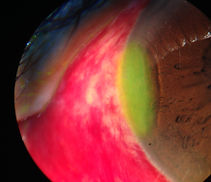

HIALOSIS ASTEROIDE FOTO POR DR. MARCO HERNÁNDEZ